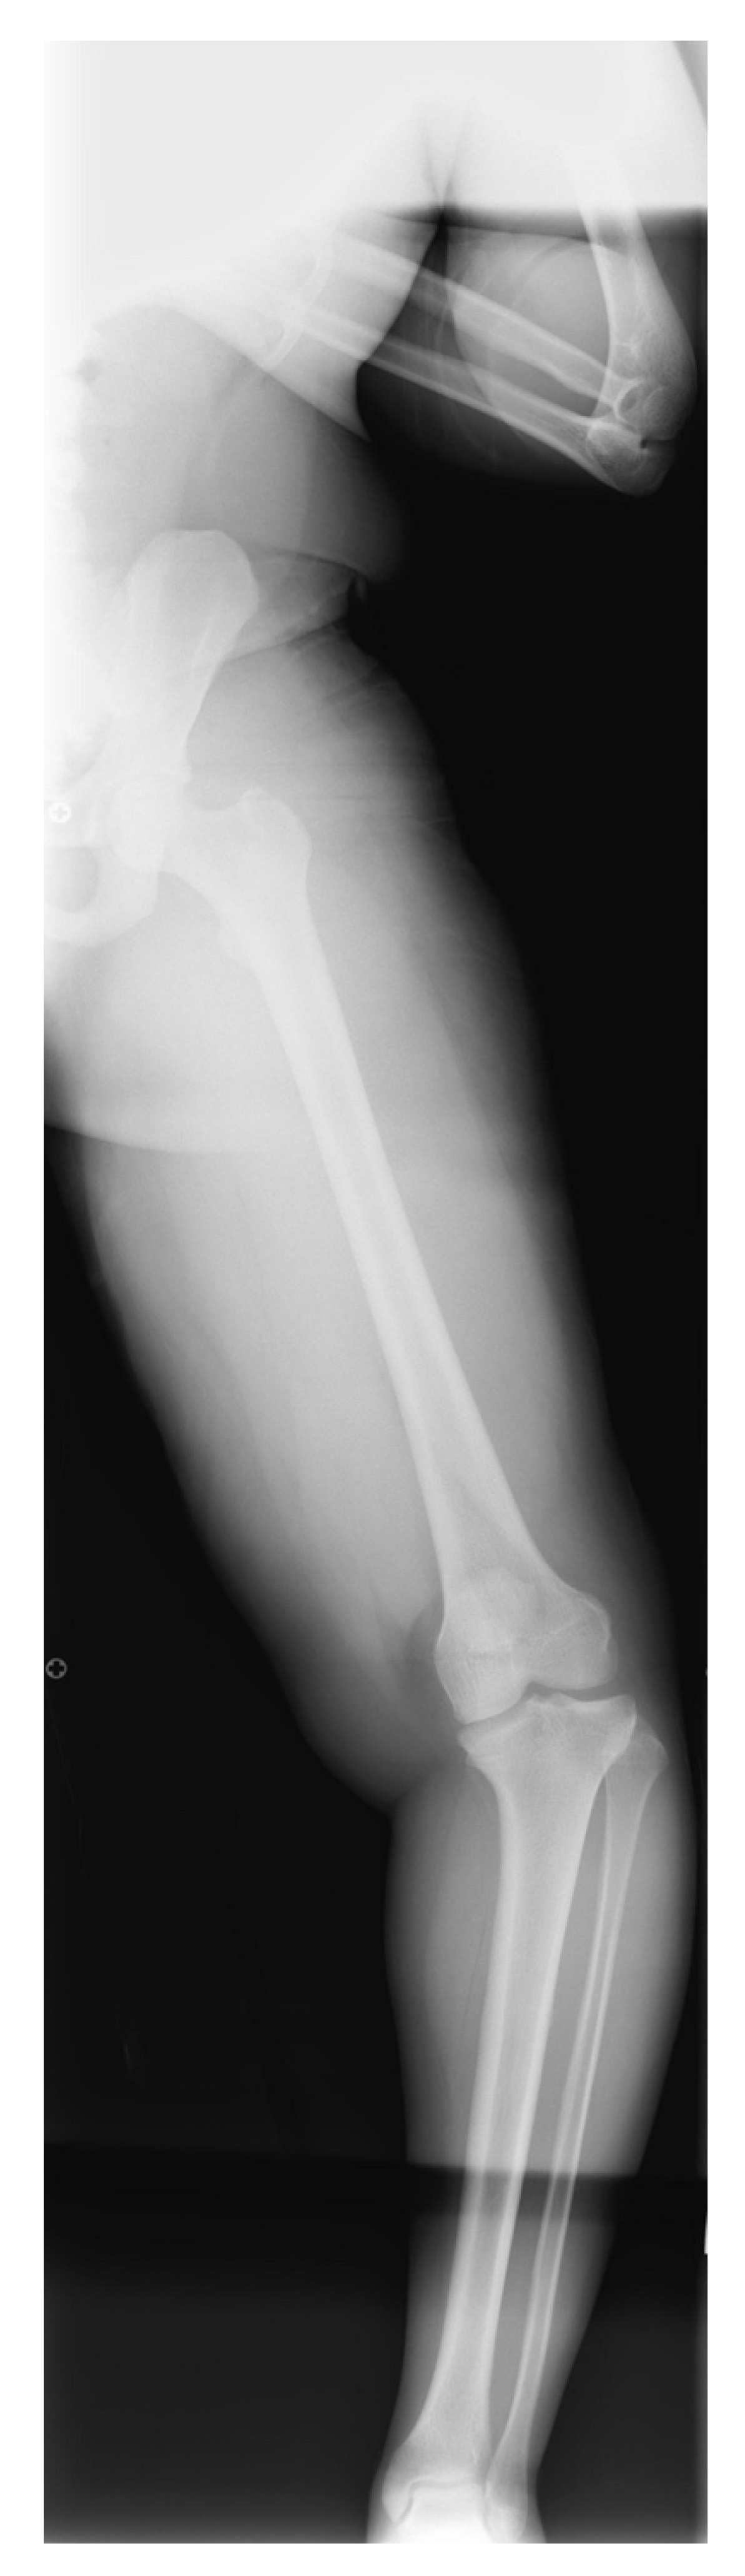

13. Osteotomies with Acute Correction

17. Gradual Correction with External Fixation